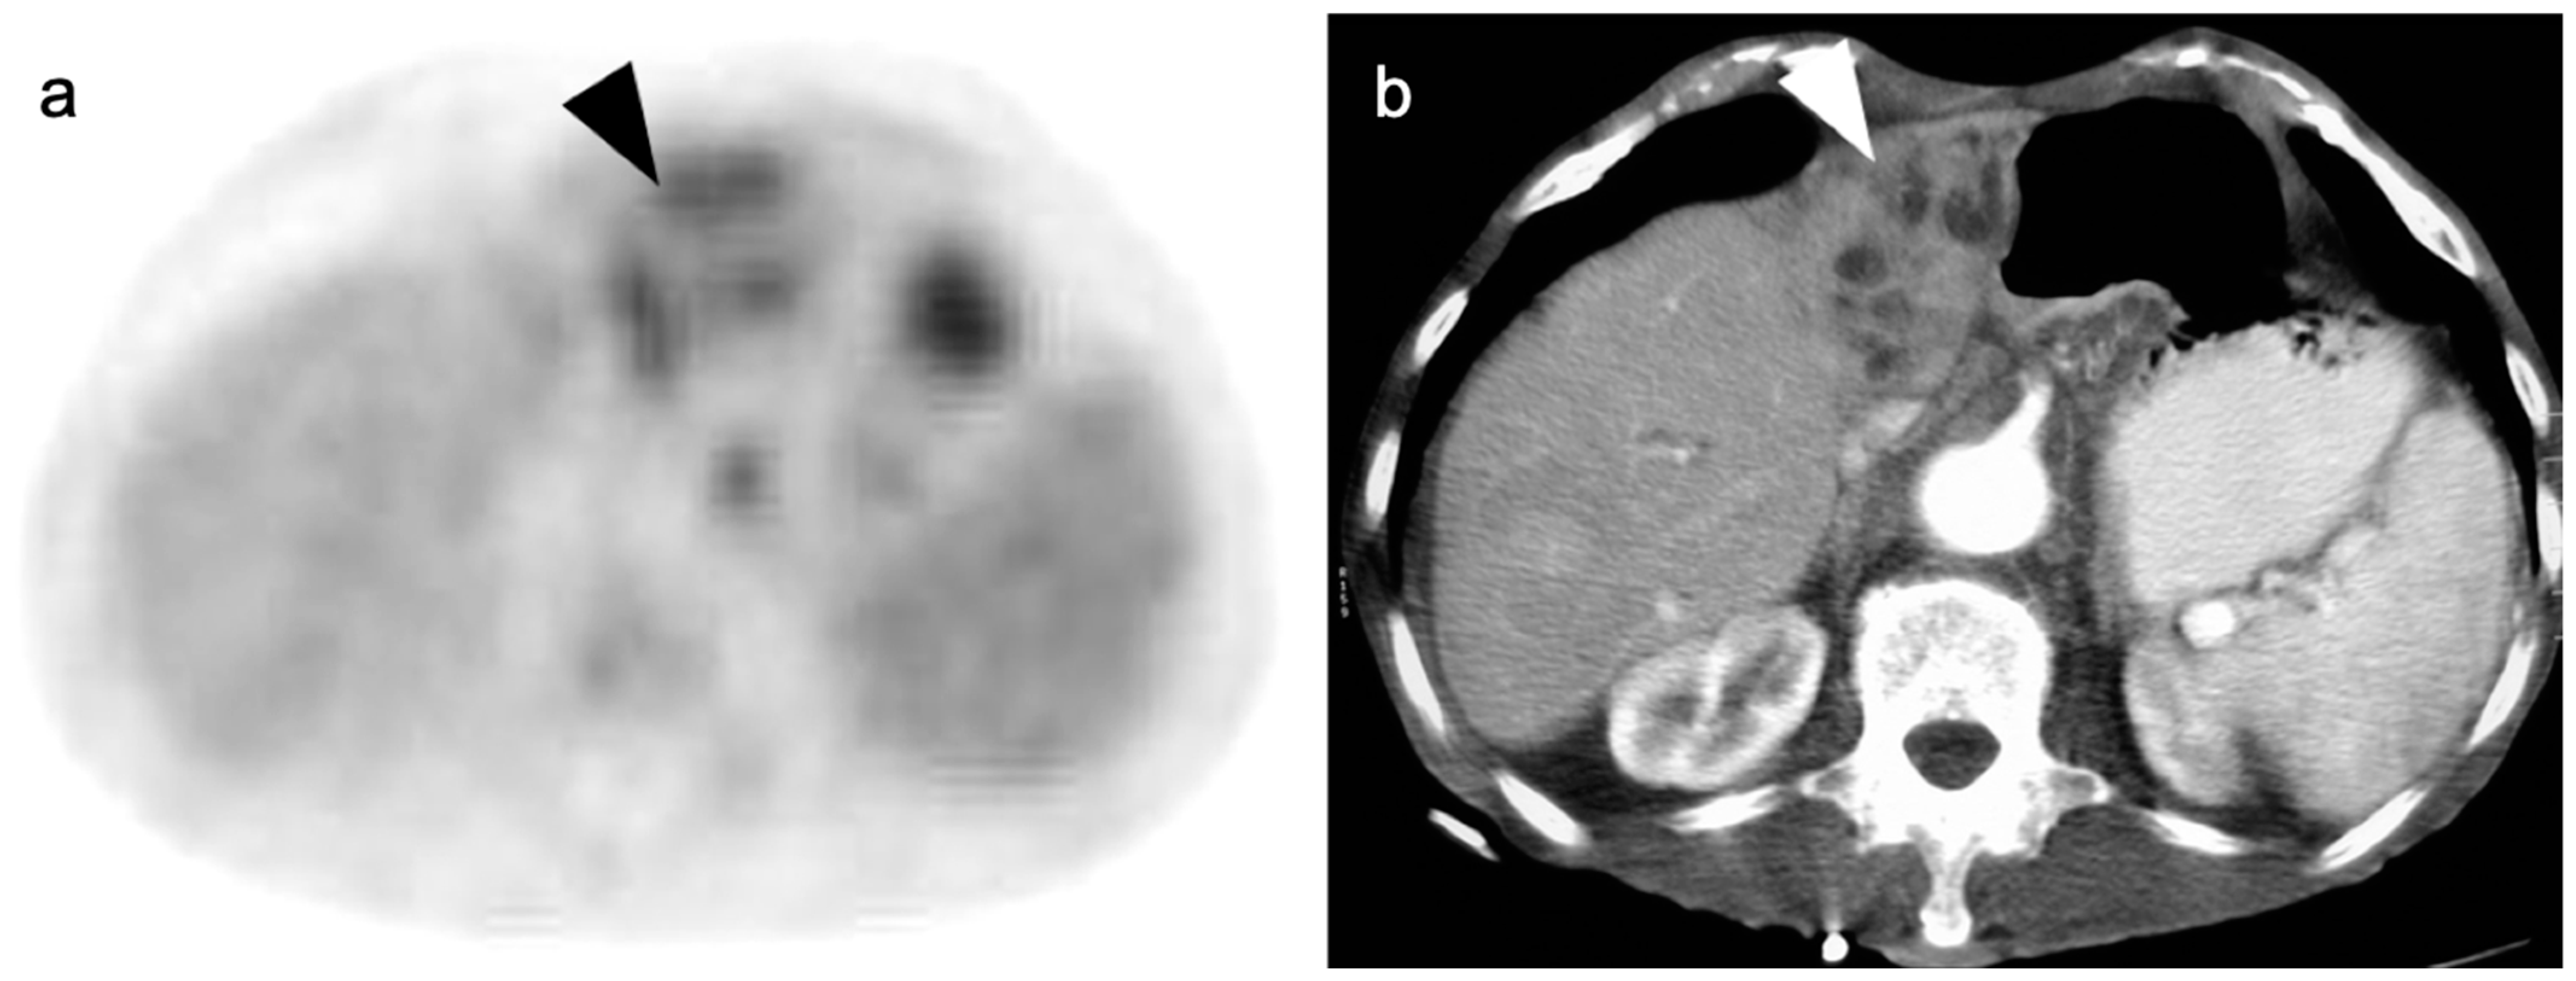

5. Cholangiocarcinoma

- Kluge, R.; Schmidt, F.; Caca, K.; Barthel, H.; Hesse, S.; Georgi, P.; Seese, A.; Huster, D.; Berr, F. Positron emission tomography with [18F]fluoro-2-deoxy-D-glucose for diagnosis and staging of bile duct cancer. Hepatology 2001, 33, 1029–1035. [Google Scholar] [CrossRef]

- Kim, J.Y.; Kim, M.-H.; Lee, T.Y.; Hwang, C.Y.; Kim, J.S.; Yun, S.-C.; Lee, S.S.; Seo, D.W.; Lee, S.K. Clinical Role of 18F-FDG PET-CT in Suspected and Potentially Operable Cholangiocarcinoma: A Prospective Study Compared with Conventional Imaging. Am. J. Gastroenterol. 2008, 103, 1145–1151. [Google Scholar] [CrossRef]

- Fong, Z.V.; Brownlee, S.A.; Qadan, M.; Tanabe, K.K. The Clinical Management of Cholangiocarcinoma in the United States and Europe: A Comprehensive and Evidence-Based Comparison of Guidelines. Ann. Surg. Oncol. 2021, 28, 2660–2674. [Google Scholar] [CrossRef]

- Kiefer, L.S.; Sekler, J.; Gückel, B.; Kraus, M.S.; la Fougère, C.; Nikolaou, K.; Bitzer, M.; Gatidis, S.; Pfannenberg, C. Impact of 18F-FDG-PET/CT on Clinical Management in Patients with Cholangiocellular Carcinoma. BJR Open 2021, 3, 20210008. [Google Scholar] [CrossRef] [PubMed]